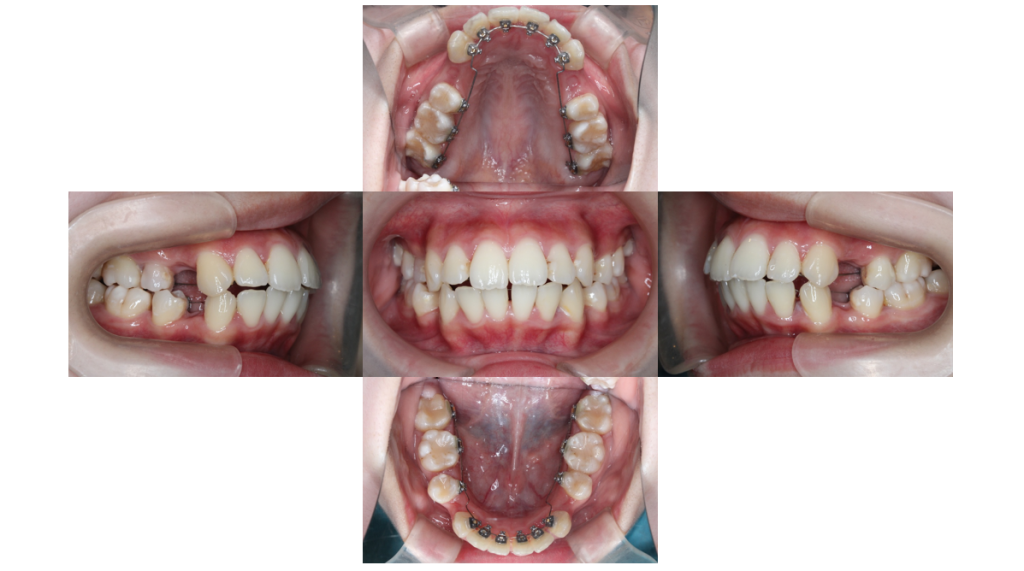

2ヶ月経過

叢生・裏側矯正の症例バネで広げていた前歯にも装置が付きました。

3ヶ月経過

叢生・裏側矯正の症例上顎と同じようにバネで広げていた下顎前歯部にも装置が付きでこぼこが解けてきました。